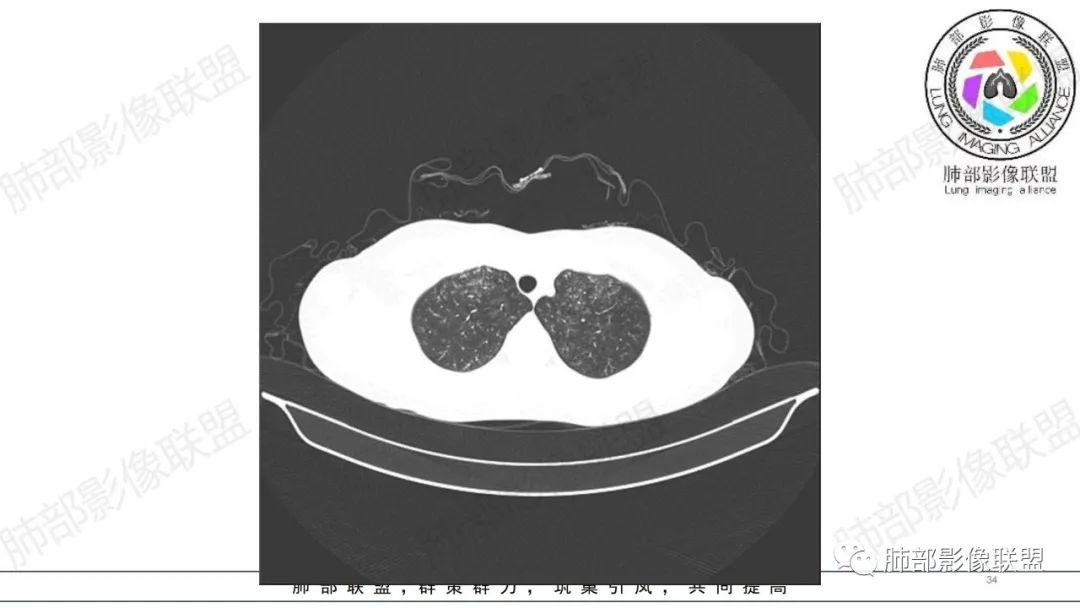

34岁女性患者,“哮喘”病史30年,近期有可疑刺激性气体吸入史;因乏力半年,咳嗽、憋气、发热4天就诊;6.1CT提示双肺广泛毛玻璃影及粟粒样结节,胸膜下闲置及血管周闲置,可见树丫征,部分小叶间隔增厚。考虑:1.过敏性肺泡炎,有可疑刺激气体接触史,胸膜下闲置,广泛毛玻璃影,地图样分布,粟粒结节边界模糊,支持过敏性肺泡炎,但糖皮激素治疗效果不佳,且动态复查血常规血红蛋白进行性降低,过敏性肺泡炎 不符合;2.肺含铁血黄素沉积症:患者30“哮喘”病史,可能为肺含铁症状,肺部CT提示双肺弥漫毛玻璃影及粟粒结节影,中下肺明显,肺底部分小叶间隔增厚,近期咳嗽、憋气、发热,血常规血红蛋白进行性下降,考虑肺含铁急性期症状,但临床无咯血症状,肺含铁不典型。综合考虑:肺含铁血黄素沉积症>过敏性肺泡炎。

年轻女性 ,急性喘息发热,肺部影像弥漫磨玻璃密度,部分细小腺泡结节,胸膜下黑线显示,短期复查,病变密度增高,下肺明显,血管周围肺组织累及较少、且逐渐成小叶间隔分布。考虑弥漫肺泡内病变,并经淋巴道转移,下肺比上肺明显,多为免疫细胞功能下肺较强。1.过敏性肺泡炎,有相关病史,三层密度特点、头尾测分布,符合。2 肺泡微石症,多有钙化,且缓慢起病,病程不太符合,放待排。3 吸入相关肺损伤,有病史,疾病演变过程也符合渗出-肉芽肿改变,建议详细询问病史。4 感染性病变,结核?病变气道分布为主,如此弥漫且没有树丫不符合。5.巨细胞病毒,可以磨玻璃 结节 改变,没有免疫缺陷病史。最后考虑吸入所致 1过敏性肺泡炎、吸入性肺损伤 鉴别肺泡微石症。

年轻女性,两肺多发磨玻璃影,沿气道至肺泡分布,考虑过敏性肺泡炎可能性大。